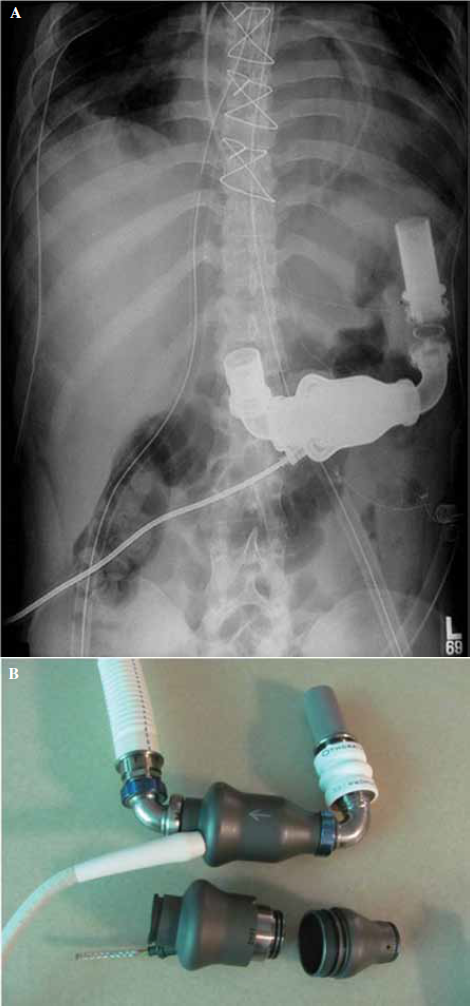

En el período del estudio resultaron implantados 68 DAVI, siendo excluidos 4 pacientes por diversas razones, representando los 64 restantes la población del estudio. Cincuenta y siete (89,1%) pacientes recibieron un dispositivo Heart Mate II (St Jude Medical, St Paul, MN, USA) (Figura 1) y los otros 7 (10,9%) pacientes un dispositivo HeartWare (HeartWare Inc, Framingham, MA, USA) (Figura 2), realizándose concomitantemente al implante del DAVI, 2 plásticas mitrales y 2 reemplazos valvulares mitrales en el mismo acto quirúrgico. Cincuenta y tres (82,8%) pacientes recibieron el DAVI como puente al trasplante mientras que los 11 (17,2%) restantes fueron utilizados como terapia de destino.

En todos los pacientes tratados con AM se evidencio el cambio de coloración de la orina, que se tornó verde o azulada (Figura 3). Cinco (7,8%) pacientes presentaron hipertensión arterial a posteriori de la infusión del AM, requiriendo del empleo de vasodilatadores endovenosos, 3 (9,1%) pacientes en el grupo AM frente a 2 (6,4%) pacientes en el grupo control (valor de P=0,3).